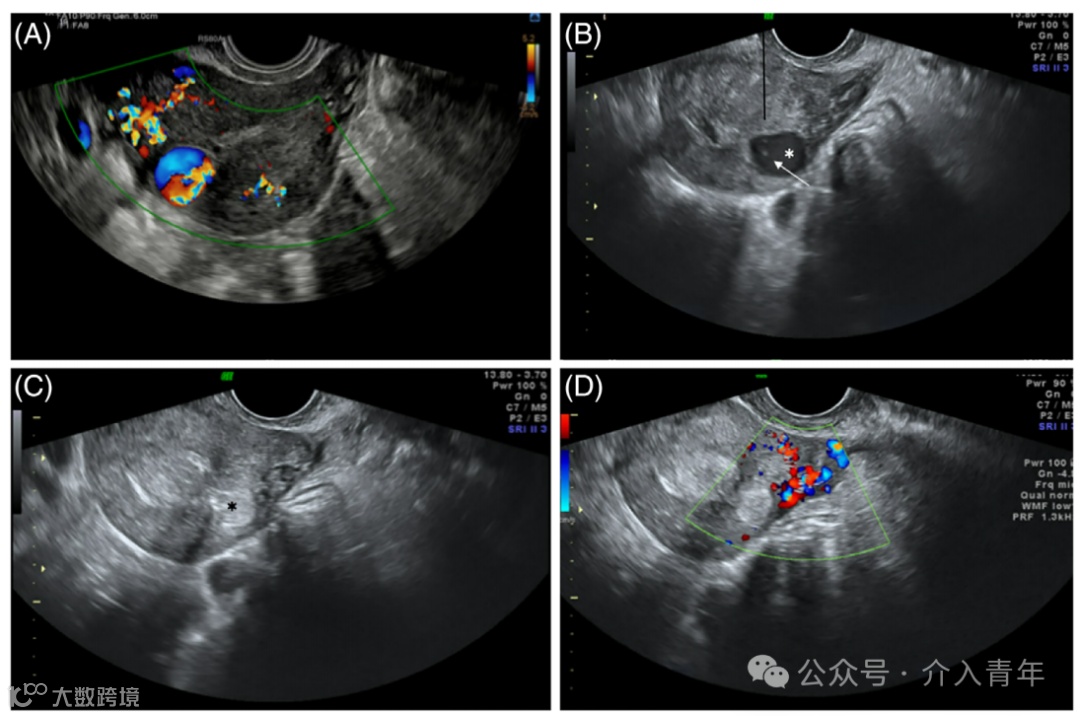

图2:子宫假性动脉瘤的经阴道超声检查。

(A)经阴道横切面超声图像显示子宫右上段肌层紧邻子宫内膜带处存在无回声假性动脉瘤。

(B)经阴道横切面彩色多普勒超声图像显示假性动脉瘤内典型的“阴阳征”。

(C)频谱多普勒分析显示来白右侧子宫动脉的主要供血动脉的动脉波形。